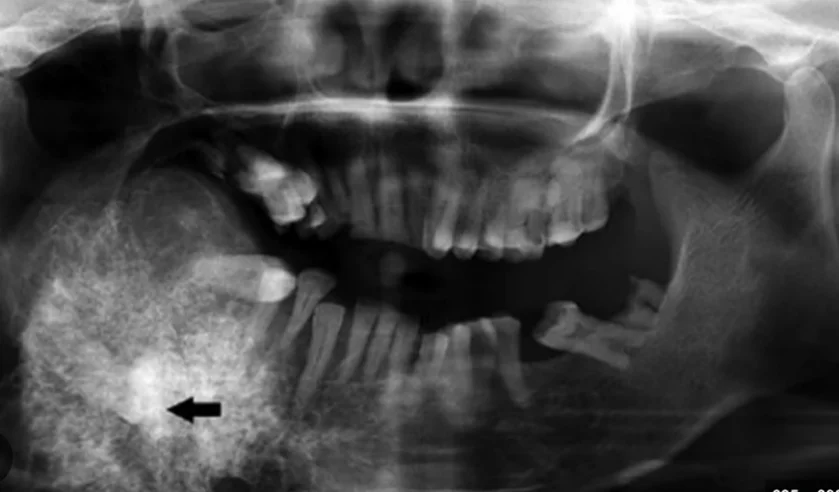

- Odontogén jóindulatú daganatok (állcsontokban): pl. ameloblastoma, odontoma (fogeredetű, gyakran röntgenen derül ki).

Szájüreg, garat vagy gége beningus tumor eltávolítása

Odontogen tumor az állkapocs csontban